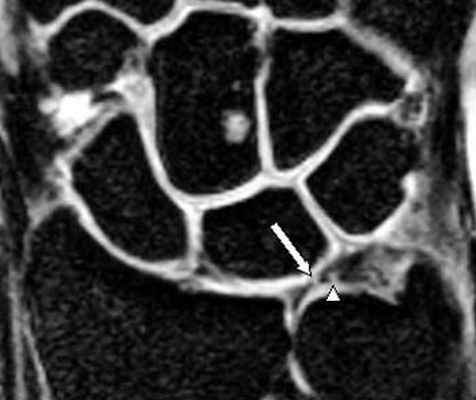

(Слева) МР-артрография в режиме Т1ВИ FS, коронарный срез: определяется разрыв тыльной части ЛПС. Контрастный препарат через дефект распространяется в среднезапястный сустав. Также отмечается разрыв треугольного фиброзно-хрящевого комплекса (ТФХК), вследствие ко торого контрастный препарат поступает в дистальный лучелоктевой сустав.

(Справа) МР-артрография в режиме Т1ВИ FS, коронарный срез, этот же пациент: определяются разрывы мембранозной части ЛПС и мембранозной части треугольного фиброзно-хрящевого диска. (Слева) МР-артрография в режиме Т1ВИ FS, аксиальный срез: визуализируется интактный тыльный пучок, ладонный пучок поврежден. Следует отметить расширение суставной щели, истончение хряща и кисто-зоподобную перестройку.

(Слева) МР-артрография в режиме Т1ВИ, коронарный срез: визуализируется крупный дефект ЛПС. Суставная щель расширена. Следует отметить наличиедегенеративных перфораций в центральной части ТФХК.

(Справа) МР-артрография в режиме Т2ВИ FS, коронарный срез: визуализируется крупный дефект ЛПС. Суставная щель расширена. Следует отметить неравномерное истончение хряща и кистозные изменения суставных поверхностей, обусловленные нестабильностью. Это говорит о том, что разрыв данной связки был биомеханически значим. (Слева) Артрография в заднепередней проекции: распространение контрастного препарата через дефект ЛПС в среднезапястный сустав. ПТС интактна.